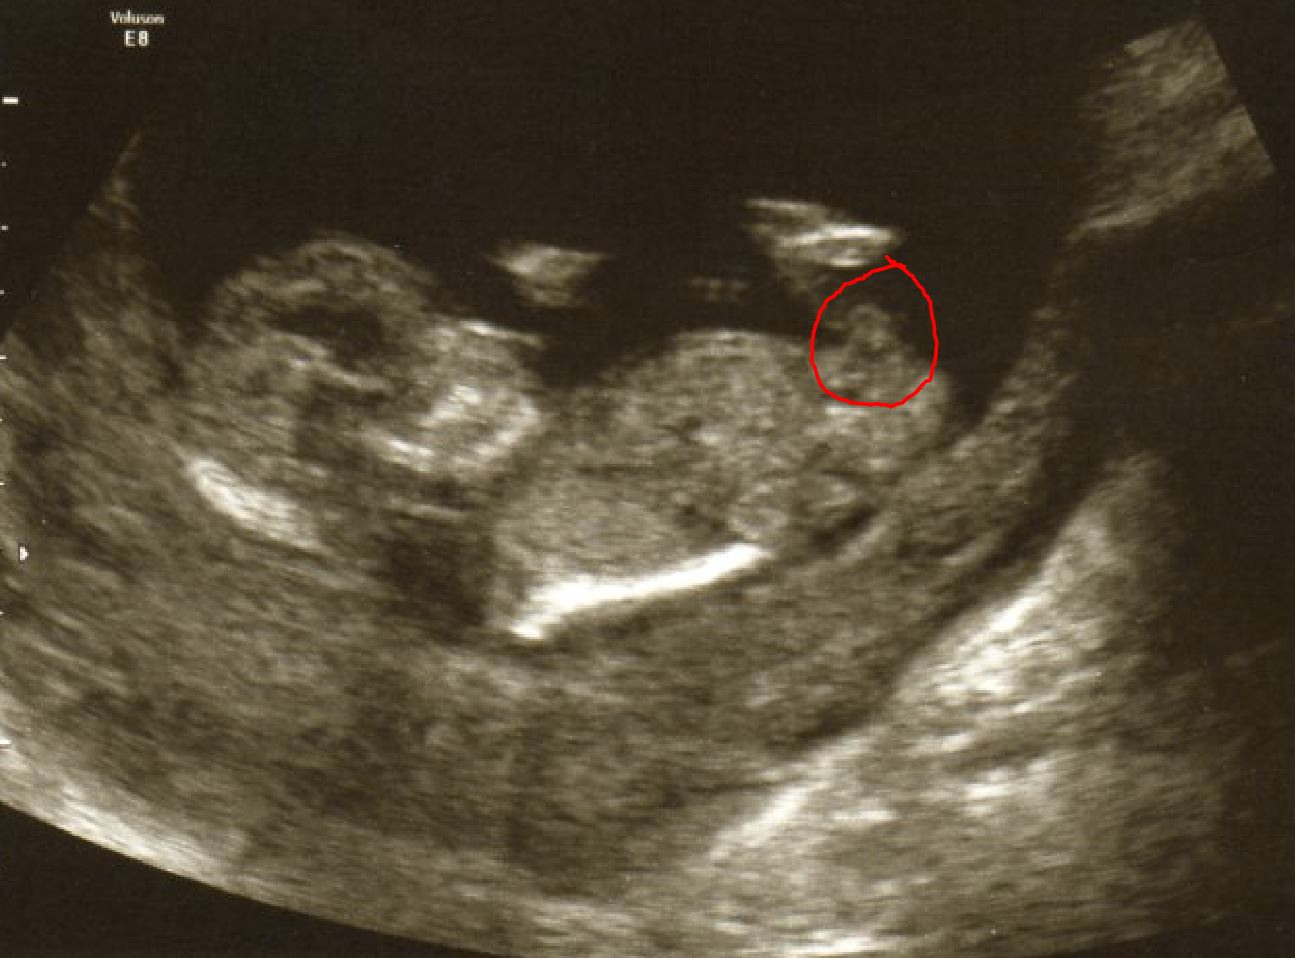

I am new to all this "nub theory" stuff but was wondering am I right in thinking the nub is where I have circled with a red line in the 2 pictures both at 12 weeks + 5 days. To see the picture bigger right click on the picture and select "Open image in new tab" you will see the actual size.

Pic 1

Attachment 13132